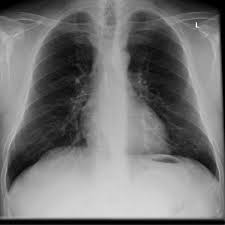

endoscopic examinationX-ray examinationmanometryEndoscopy ( mirroring)May already indicate leftovers, inflammation or a visible narrowing of the lower esophagus to achalasia. In the diagnosis of achalasia is an endoscopy , which is a reflection of the esophagus and stomach , but especially important to rule out other possible causes for the symptoms - surely exclude - such as esophageal cancer. In some cases, the doctor takes out in this study to the same tissue samples (called biopsies) in order to examine them for changes and abnormalities.X-rayThus, the X-ray examination can help diagnose achalasia , get people out of the X-ray contrast agent ( Breischluck ), which makes the course of the esophagus visible on the radiograph . In achalasia is found in the X-ray image of a tapered narrow at the transition to the stomach . Depending on the stage of the disease , the area of the esophagus is dilated above the narrow (so-called champagne glass ) .